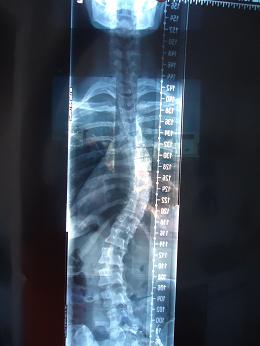

aktuelles Röntgenbild (2.11) oberer Bogen 45°, unterer Bogen 41°